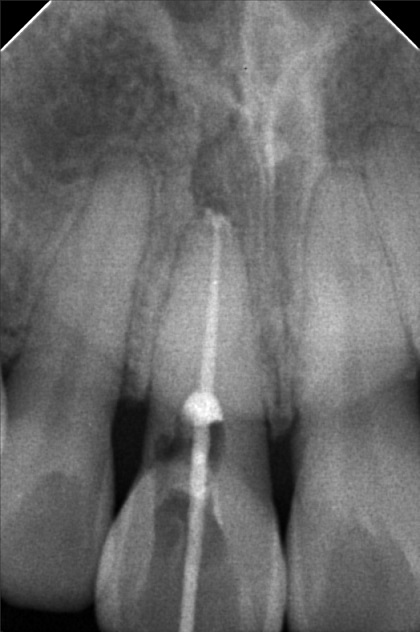

- Procedure

- 5/21/22- OP & XRAY 6/14/22 - RCT / Eugenol 6/21/22- EDTa / tf 8/17/22 - FILE #25 20mm; Irrigate/ EDTA/ TF 8/20/22- guttapercha 30/ 21.5mm/ obturation with MTA veneer 11 shade- opaquer/ A3 cervical body A2/ insical 08/08/23-LC #35 Distal,Cervical Caoh/LC #37 Mesial,OP,X-ray/anesthesia 08/26/23- for RCT #35 / Check up 06/14/24 Op(heavy) #35 alumina crown 06/21/24 Install of crown 12/20/24 OP heavy LC #34 occ. deep 05/15/26 OP w/airpolish